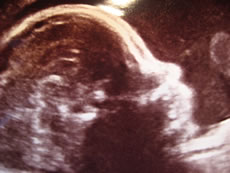

Ultraschallbild: Dat Kind hett Köpfchen!

Klock teihn hebbt de Hebamme Lydia un ik uns drapen, ¼ Stünn later stünnen wi vör en schwanger Frau, de to Vörsorge-Ünnersöken kamen weer. Ik dörv ehr glieks den Blootdruck meten un den Ümfang vun ehren Buuk. De Hebamme hett de warden Mudder an en CTG-Gerät anslaten un Herztöne vun't Baby kontrolleert un dat Doon vun de Gebärmutter prüft. Dor klingel miteens datUltraschall: Allens okay! Notfall-Telefon. Een vun Lydias Fruun weer graad in't Krankenhuus inlevert. Se harr Wehen kregen un weer dor nu an't Dauer-CTG anslaten.